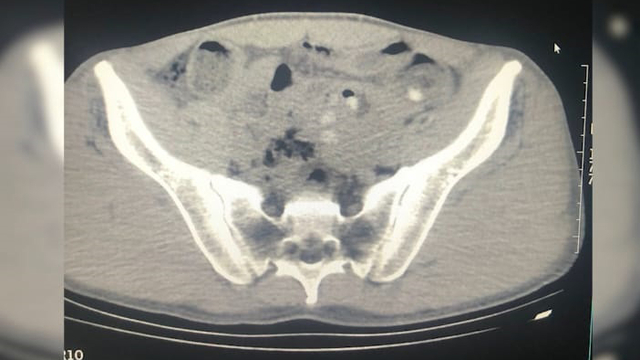

İl Emniyet Müdürlüğü Narkotik Suçlarla Mücadele Şubesi ekipleri, Tatvan ilçesindeki uygulama noktasında yol kontrolü sırasında bir yolcu otobüsünü durdurup, arama yaptı. Ekipler, şüpheli hareketleriyle dikkat çeken yabancı uyruklu 3 kişinin sırt çantalarında yaptığı aramada 109 parça halinde metamfetamin ele geçirildi. Gözaltına alınıp hastaneye götürülün şüphelilerin çekilen röntgenlerinde de midelerinde 45 kapsül metamfetamin tespit edildi. Şüphelilerin midesindeki uyuşturucu doğal yollarla çıkarıldı.